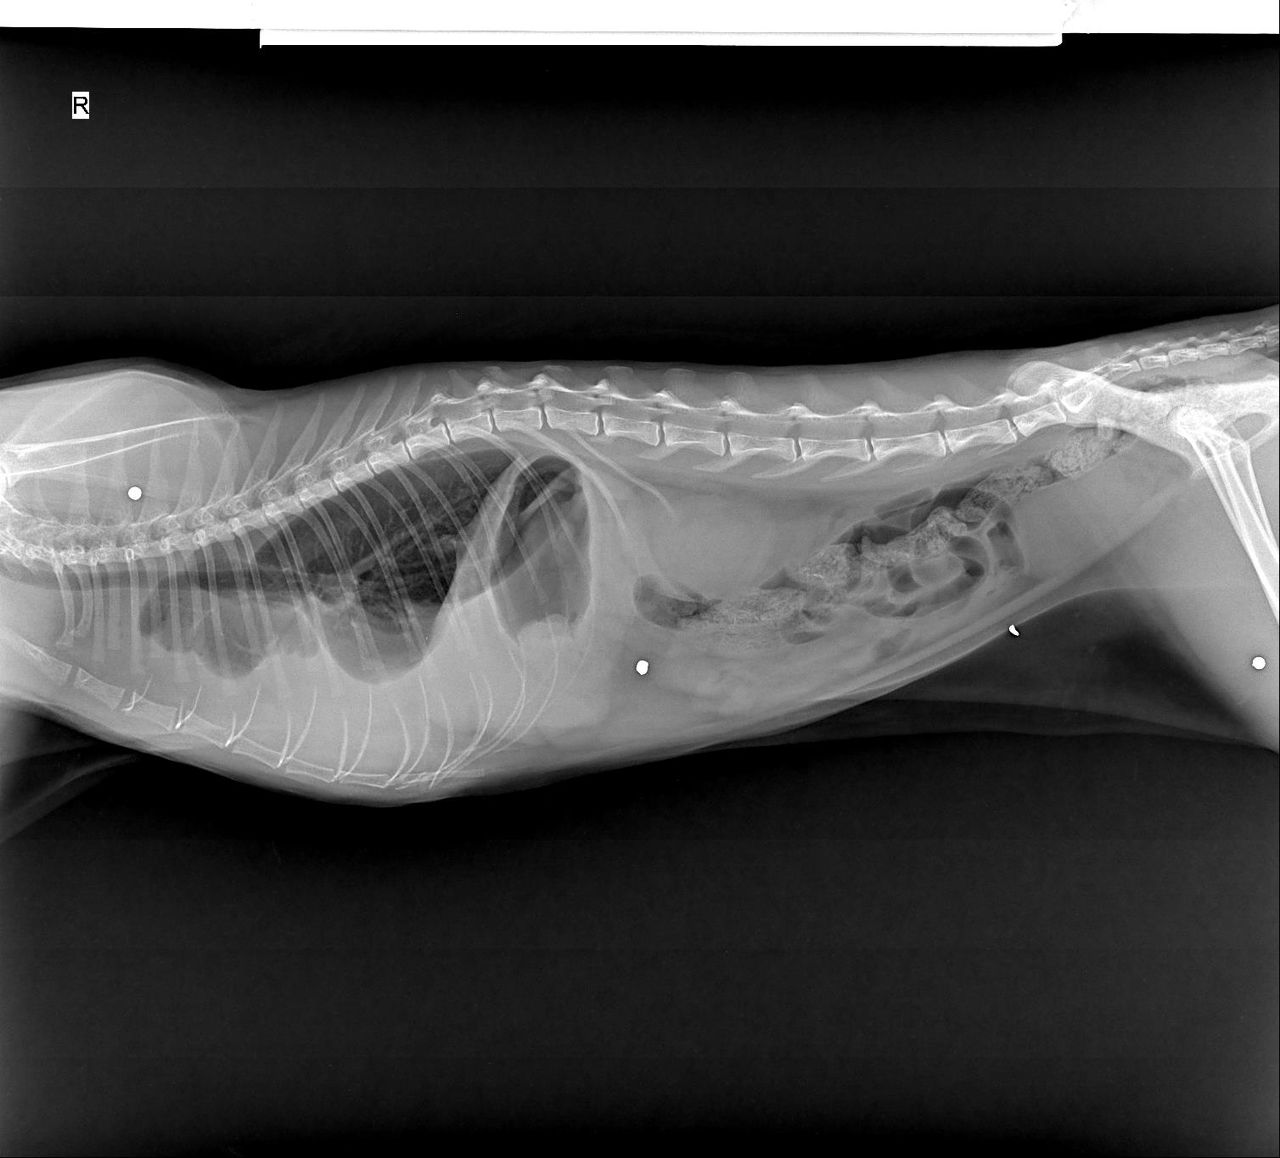

«В своей практике я довольно часто сталкивалась с подстреленными кошками. Большинство из них спасти не удалось. Некоторые до сих пор живут с пулями в теле. Это страшно — видеть, как животные страдают из-за человеческой жестокости. На фотографиях — рентгеновские снимки, на которых видны застрявшие пули. Кроме того, в уставе муниципального предприятия “Тазалык” прямо указано положение об “отстреле кошек”, а не только собак. А в текстах тендеров на проведение мероприятий по отстрелу животных в пригородных районах также упоминается отстрел кошек».